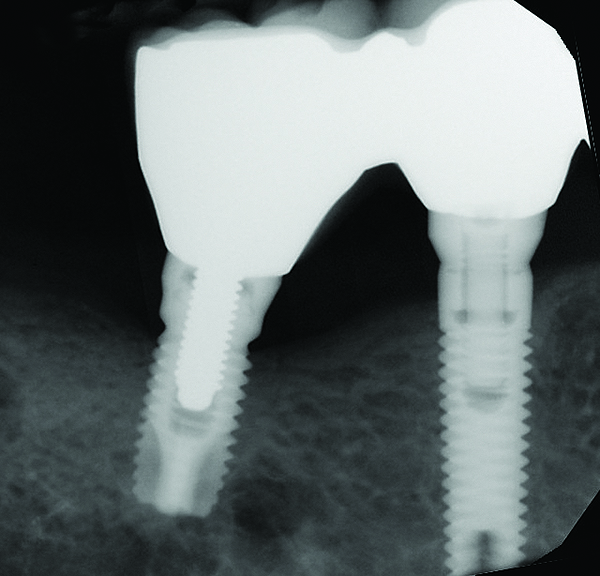

Fig 7 through Fig 14. Periapical radiographs of a 62-year-old woman who received a fixed porcelain-fused-to-metal reconstruction supported by abutments by internally connected dental implants. Fig 7 through Fig 10 are at initial prosthesis placement: mandibular site Nos. 30 and 29 (Fig 7); mandibular site Nos. 26, 25, and 23 (Fig 8); mandibular site Nos. 23 and 21 (Fig 9); mandibular site Nos. 21 through 19 (Fig 10). Fig 11 through Fig 14 are 11 years later (2013) and show excellent preservation of the vertical bone levels around the implants: mandibular site Nos. 30 and 29 (Fig 11); mandibular site Nos. 26 and 25 (Fig 12); mandibular site Nos. 25 and 23 (Fig 13); mandibular site Nos. 20 and 19 (Fig 14). It is interesting to note that in the mandibular right posterior quadrant there is a matched pair, ie, an external hex dental implant (No. 30) adjacent to an internally connected dental implant (No. 29). The bone levels around each of these designs are well-preserved at the 11-year follow-up.